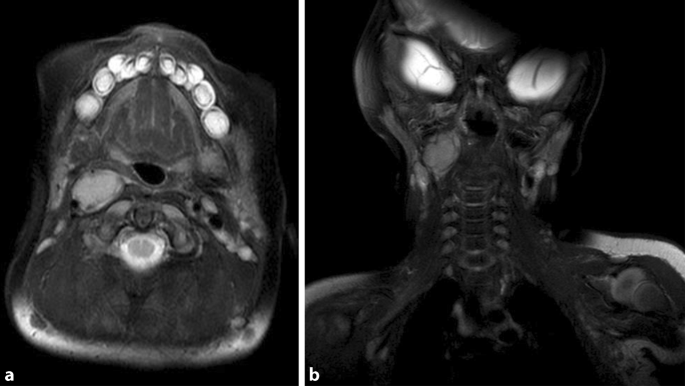

Kongenitales Horner Syndrom Springerlink